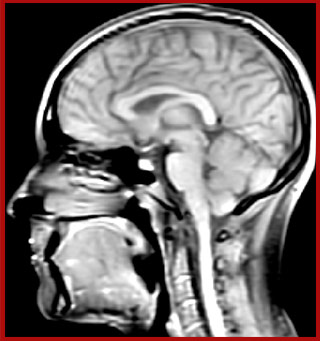

of limiting MWI to the brain, even without the cerebellum, we can now spend about the same amount of time and scan the whole brain and the cervical spinal cord, which is a huge boost for us.” Dr. Rauscher says, “For MWI we perform 3D T2 with 32 or more echoes. This used to take a long time, but with Compressed SENSE we can decrease this to ten minutes for the whole head. Because of the large field of view (FOV) on the readout direction, we even get information from the brainstem, which we previously missed when we were using the GRASE approach. Having the whole head scan is nice because it has spatial resolution, orientation and FOV that are comparable to the standard 3D clinical MS scans, including the FLAIR and 3D T2, and a 3D T1 for brain volume.”

The techniques for measuring myelin have changed a lot over the years. “Since we are using the Elition, our myelin water images are much better. We're now acquiring 1 x 2 x 5 mm voxels and displaying at 1 x 1 x 2.5 mm. For a whole brain we can now measure the fraction of water in the myelin component in only about five or six minutes,” Dr. MacKay says.

T1 - Weighted, Myelin Water Fraction Superimposed

Spinal cord coverage

Smaller, more isotropic voxels

Excellent detail in quantitative maps

Images courtesy of Adam Dvorak, Department of Physics and Astronomy, University of British Columbia